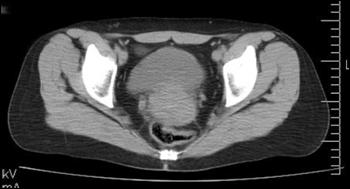

b). Neoplasm de col uterin, invaziv in vezica urinara

a. b.

a) Tumora de col uterin, invaziva in vezica urinara - pacienta s-a prezentat in anurie; b) Tumora de col uterin, operata (histerectomie totala + iradiere), recidivata, invadand vezica urinara si rectul - pacienta s-a prezentat cu hematurie